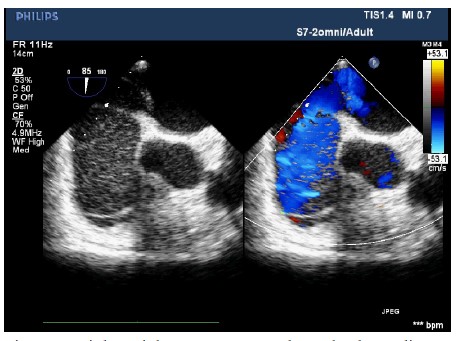

The patient entered the operating room and her ECG was monitored regularly. The induction of anesthesia was smooth. When the surgical team was manipulating the fracture, her blood pressure (BP) suddenly decreased to 63/43 mmHg, heart rate increased to 112 beats/min, and the saturation of pulse oxygen (SpO2) fell to 72%. 1 mg methoxamine was used to raise the blood pressure without success. 2 mg methoxamine, 6 mg ephedrine, and 8 μg nonadrenaline were subsequently given without significant blood pressure change. The central venous pressure was 15mmHg. In addition, the end tidal carbon dioxide decreased to 10 mmHg. There were no significant airway pressure changes. While an allergic reaction was initially suspected, no dermatological changes were identified. Emergency blood gas indicated a partial pressure of artery carbon dioxide (PaCO2) of 77.9 mmHg, and an oxygen partial pressure of 67mmHg. Potential pulmonary embolism was suspected. A transesophageal echocardiography (TEE) was followed. It revealed an enlarged right atrium (Figure1), hypokinesia of the free right ventricle wall, and poor filling of left ventricular. The ratio of left/right ventricular apparent disorder and the pressure of tricuspid valve was 51mmHg with massive regurgitation of 3.57m/s (Figure 2). Severe tricuspid reflux was also observed (Figure 3). Epinephrine and milrinone along with high-dose vasopressin were initiated. While no thrombi in the pulmonary or right ventricle were identified, unstable hemodynamics, changes in carbon dioxide, findings in TEE strongly suggested a possible major PE. Extracorporeal membrane oxygenation (ECMO) was immediately established and an emergent pulmonary thromboembolectomy was successfully performed. The patient was transferred to the surgical intensive care unit for monitoring and evaluation. The patient was discharged without residual deficits after 20 days in surgical intensive care unit.

Figure 3: Tricuspid valve regurgitation on 2D-transesophageal echovardiography. Severe beam of tricuspid valve regurgitation was observed.